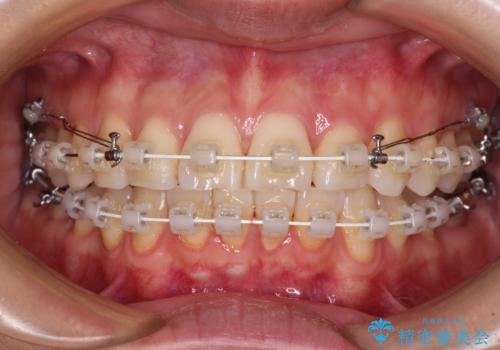

- 矯正装置

- 審美装置

- 奥歯の咬み合わせと、上下前歯の隙間を気にして来院された患者様です。

上顎の歯列全体が、下顎歯列に対して前方に位置しており、その影響で上顎前歯がやや前方に突出している状態でした。

横顔の印象から、抜歯をして積極的に口元を引っ込める必要はなかったため、アンカースクリューを用いて上顎歯列全体を後方に移動させることとしました。

奥歯の咬み合わせは理想的な状態に改善され、その結果として上下歯列もバランスの良い位置に収めることができました。

若干ではあるものの上顎前歯を内側に移動させることができ、以前よりも口が閉じやすいと感じるようになりました。